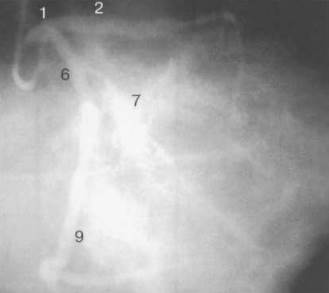

На рис. изображены левая и правая коронарные артерии и их ветви при равномерном типе коронарного кровообращения в обычной последовательности проекций.

Рис. а - Левая коронарная артерия. Правая косая проекция. б - левая коронарная артерия. Переднезадняя (АР) проекция с краниальным склонением 30°.

Рис. а - левая коронарная артерия. Правая косая проекция с краниальным склонением. б - левая коронарная артерия в проекции «паук» — левое каудальное склонение.

1 — левая коронарная артерия; 2 — проксимальная треть передней нисходящей артерии; 3 — первая диагональная ветвь передней нисходящей артерии; 4 — дистальная часть передней нисходящей артерии; 5 — септальная ветвь передней нисходящей артерии; 6 — проксимальная часть огибающей артерии; 7 — первая маргинальная ветвь огибающей артерии; 8 — промежуточная артерия; 9 — дистальная часть огибающей артерии; 10 — проксимальная часть правой коронарной артерии; 11 — ветвь синусного узла правой коронарной артерии; 12 — ветвь острого края правой коронарной артерии; 13 — бифуркация правой коронарной артерии; 14 — правая левожелудочковая ветвь правой коронарной артерии; 15 — задняя нисходящая ветвь правой коронарной артерии.